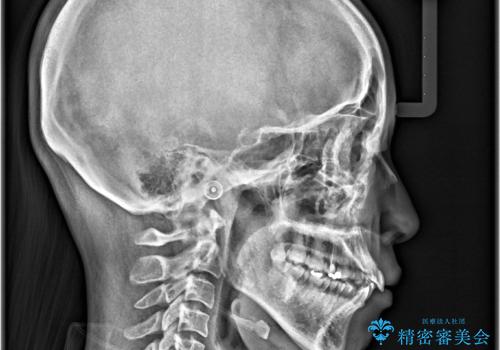

- 「歯のデコボコと前歯が出ているせいで口が閉じにくい」を主訴に来院された患者様です。

上下左右の4番(第一小臼歯)を抜歯をし審美ワイヤー装置で治療を行いました。

抜歯矯正により歯列のデコボコ(叢生)が改善し、前歯の突出も解消されたことで口元が下がり、すっきりとした印象となりました。